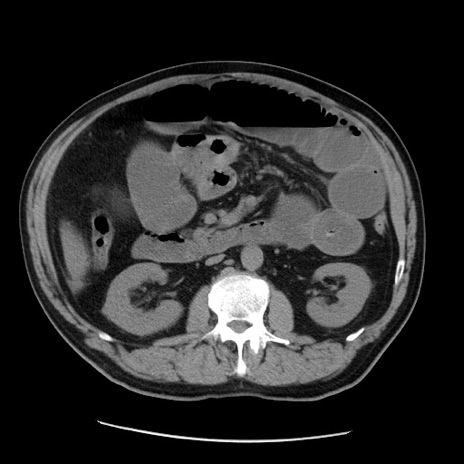

症例20(横断像)

【症例】 60歳代男性

【主訴】 腹部膨満、嘔吐

【現病歴】5日前頃より倦怠感を認め食事量減少し4日前の朝嘔吐、食事摂取困難となった。 3日前近医受診し点滴施行され整腸剤などを処方された。 当日他院を受診し、腹部膨満著明、炎症反応の上昇(CRP10.8、WBC11200)あり、紹介受診となる。

【身体所見】 意識JCS1 受け答えがはっきりしないBP 111/57mHg、 P 67bpm、、BT35.2°C、SpO2 97%(RA)、 腹部:膨隆、打診で鼓音あり、全体的に圧痛有り、腸蠕動音(-)、反跳痛ははっきりせず。

【データ】WBC 11400、CRP 14.20